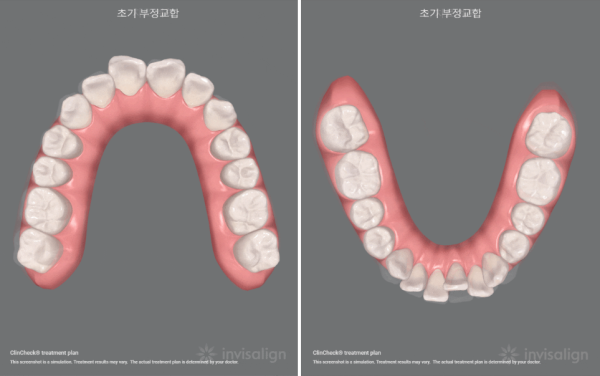

3f9194df6ce1160fd138fa6c82754705_1677244718_7488.png

교정전의 상태

3f9194df6ce1160fd138fa6c82754705_1677244724_9991.png

교정 후의 상태

이 환자분의 경우에는 비발치로 치열의 개선이 가능할 것으로 나왔습니다.

어금니의 위치를 이동시키고 그 공간으로 앞니를 뒤로 이동시키는 계획입니다.

Pre-calibration Status

post-calibration condition

In the case of this patient, it was found that it was possible to improve his teeth with non-extraction.

The plan is to move the molar position and move the front teeth back into the space.